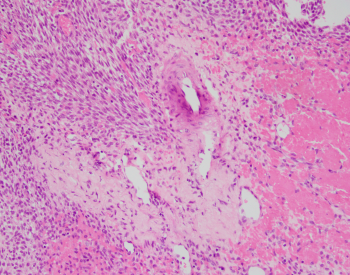

A 42-year-old female presents with nasal obstruction and a 3.0 cm polypoid nasal mass. The nasal mass shows cytologically bland spindle cell proliferation with scattered staghorn vessels and perivascular hyalinization. Provided are the H&E slides along with provided IHC including beta-catenin (tumor cells are diffusely and strongly positive for beta catenin nuclear staining, shown below) and SMA positivity (not provided). CD34 and STAT6 are negative.

Ahmed_Case_1.1_2023.jpg Ahmed_Case_2_2023.png